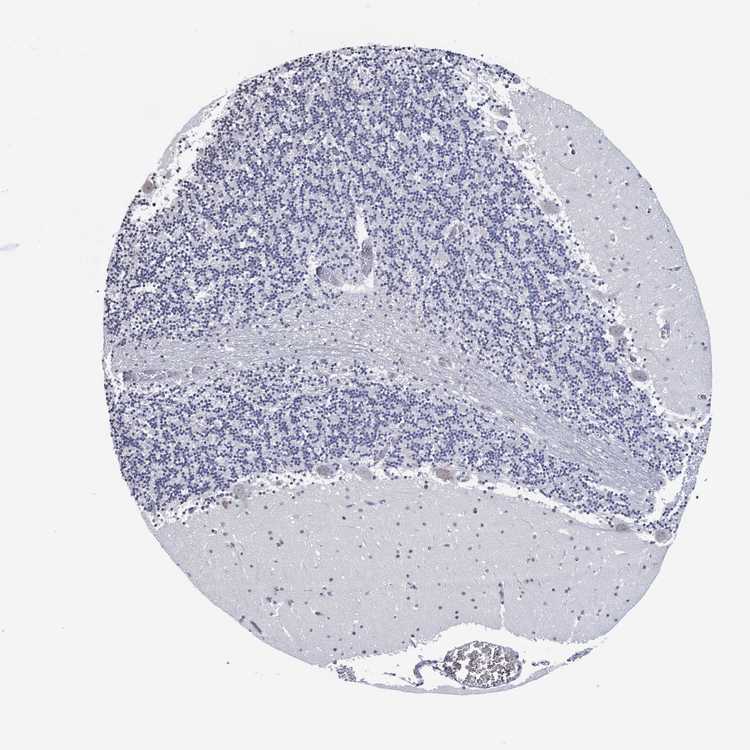

BRAIN CEREBELLUM Show tissue menu

CEREBELLUM - Expression summary

CEREBELLUM - Antibody stainingi

Antibody staining in the annotated cell types in the current human tissue is reported as not detected, low, medium, or high, based on conventional immunohistochemistry profiling in selected tissues. This score is based on the combination of the staining intensity and fraction of stained cells.

Each image is clickable and will lead to virtual microscopy that enables deeper exploration of all samples and also displays staining intensity scores, fraction scores and subcellular localization as well as patient and tissue information for each sample.

Antibody HPA002329Antibody HPA075090

Purkinje cells Not detectedLow

Cells in granular layer Not detectedNot detected

Cells in molecular layer Not detectedNot detected